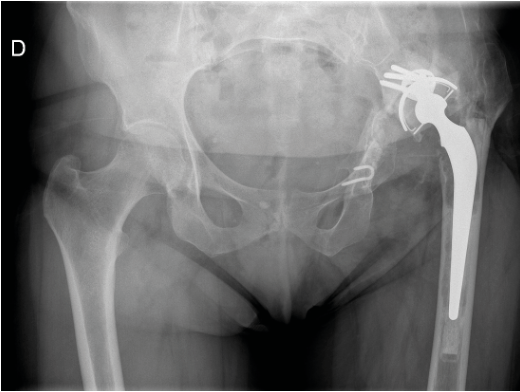

Hansson hook pins pour la fixation de fractures du col fémoral